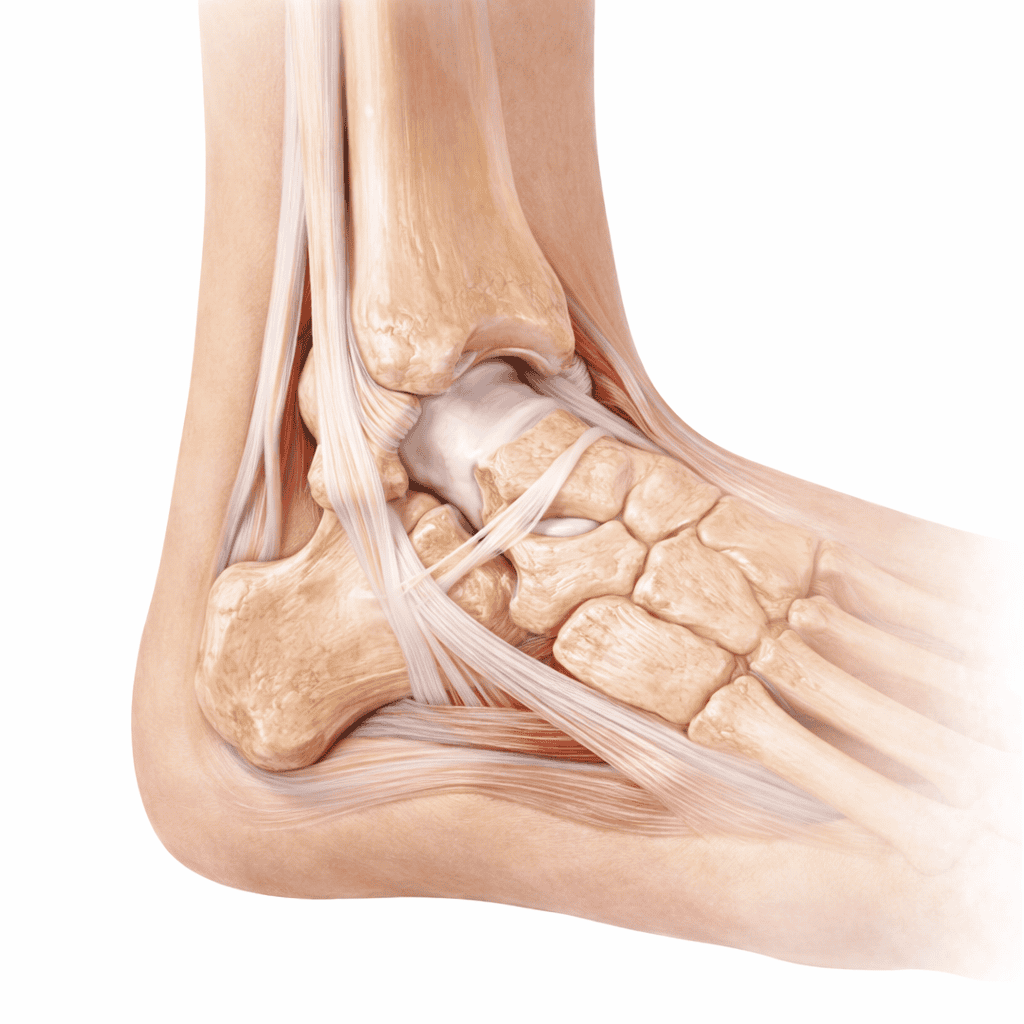

Glezna și piciorul cuprind 26 de oase, 33 de articulații și peste 100 de mușchi, tendoane și ligamente care lucrează sincronizat pentru mers, alergare și echilibru. Ligamentele laterale ale gleznei sunt cele mai frecvent lezate din corp — entorsa de gleznă este cea mai comună leziune ortopedică acută. Tendonul Achile, cel mai puternic tendon al corpului, este frecvent afectat de tendinopatie sau ruptură la sportivi și persoane active. Deformările piciorului — halux valgus, picior plat, picior cavus — produc durere cronică și afectează calitatea mersului.

Structurile gleznei și piciorului

Regiunea gleznă–picior integrează structuri osoase, ligamentare și tendinoase strâns interdependente:

- Articulația tibio-peroneală distală și tibio-talară — articulațiile principale ale gleznei; stabilizate de ligamentele colaterale lateral și medial (deltoid)

- Ligamentele laterale (LTFA, LCF, LTFP) — lezate în entorsele de inversie; ligamentul talo-fibular anterior (LTFA) este cel mai frecvent rupt

- Tendonul Achile — inserție pe calcaneu; cel mai puternic tendon al corpului; afectat de tendinopatie sau ruptură completă

- Tendoanele peronierei — stabilizatori laterali dinamici; frecvent implicați în instabilitatea cronică de gleznă

- Fascia plantară — bandă fibroasă de la calcaneu la degete; inflamarea sa produce fasciita plantară (durere matinală la călcâi)

- Primul metatars și halucele — deviere în valgus produce halux valgus (montura); cea mai frecventă deformare a piciorului